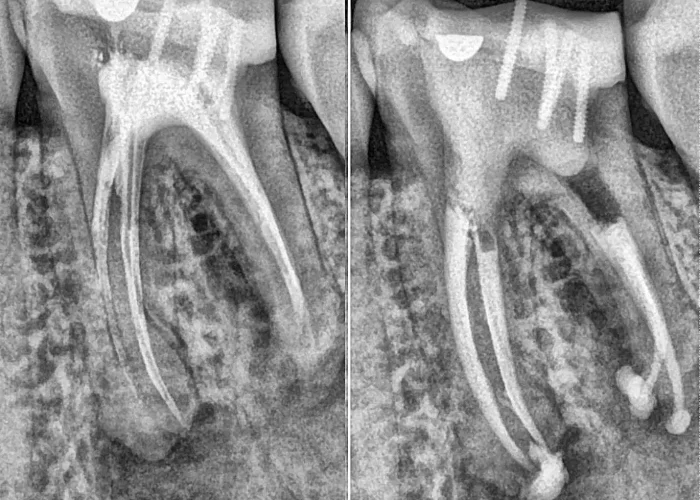

• Traitement : Un traitement endodontique (dévitalisation) est réalisé pour retirer la pulpe infectée, désinfecter les canaux radiculaires, puis les obturer. Ce soin permet de préserver la dent tout en éliminant la douleur.

Parfois, une dent déjà soignée (dévitalisée) reste douloureuse. Cela peut indiquer un échec du traitement initial ou une infection résiduelle. La douleur est souvent sourde, persistante, voire réactivée par la mastication.

• Traitement : Une reprise de traitement endodontique est effectuée. À l’aide d’outils modernes (imagerie 3D, instruments rotatifs, irrigation ultrasonique), la dent est retraitée en profondeur pour stopper l’infection.

Un examen clinique approfondi est réalisé, accompagné d’une imagerie de haute précision : radiographie panoramique, dentascan ou cone beam 3D selon la complexité. Ces outils permettent d’évaluer l’état de la pulpe, la présence d’infection et la condition des racines.